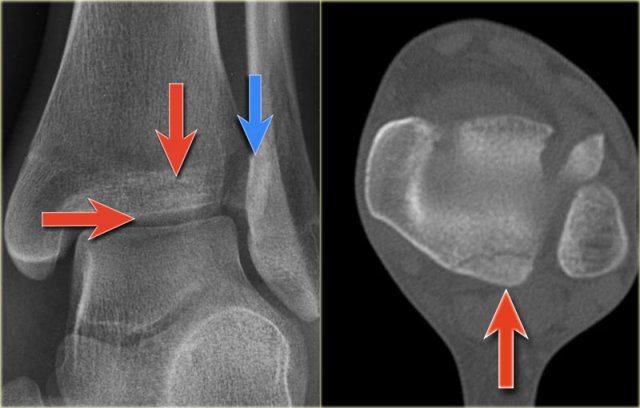

Study the images and then scroll to the next images.

The fracture through the epiphysis can be easily missed (blue arrow).

The fracture through the growth plate is only seen on CT.

Continue with the CT images.

The CT-images nicely display the fracture through the growth plate and the epiphysis.

There is only a small metaphyseal fragment, which is usually the case (red arrow).

The fracture through the epiphysis is indicated by the blue arrow.